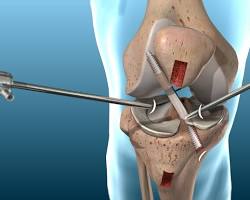

▶︎ACL手術の種類

ACL reconstruction surgery

・半腱様筋・薄筋腱を用いた再建術(ST-G移植)

・膝蓋腱を用いた再建術(BTB移植)

・その他